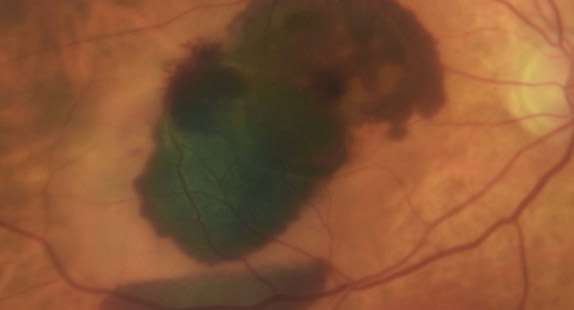

AMD is a common eye condition and a leading cause of vision loss among people age 50 and older. It causes damage to the macula, a tiny area near the center of the retina and the part of the eye responsible for sharp, central vision, which is straight ahead. In some people, AMD advances so slowly that vision loss does not occur for a long time. In others, the disease progresses quickly and may lead to a loss of vision in one or both eyes. As AMD progresses, a blurred area near the center of vision is a common symptom. Over time, the blurred area may grow larger or you may develop blank spots in your central vision.

In neovascular AMD, also called WET AMD, abnormal blood vessels grow underneath the retina. These vessels can leak fluid and blood, which may lead to swelling and damage of the macula. The damage may be rapid and severe, unlike the more gradual course of Dry AMD. It is possible to have both DRY and WET AMD in the same eye, and either condition can appear first.

With neovascular AMD, abnormally high levels of vascular endothelial growth factor (VEGF) are secreted in your eyes. VEGF is a protein that promotes the growth of new abnormal blood vessels. Anti-VEGF injection therapy blocks this growth. If you get this treatment, you may need multiple monthly injections. Before each injection, your eye will be numbed and cleaned with antiseptics.